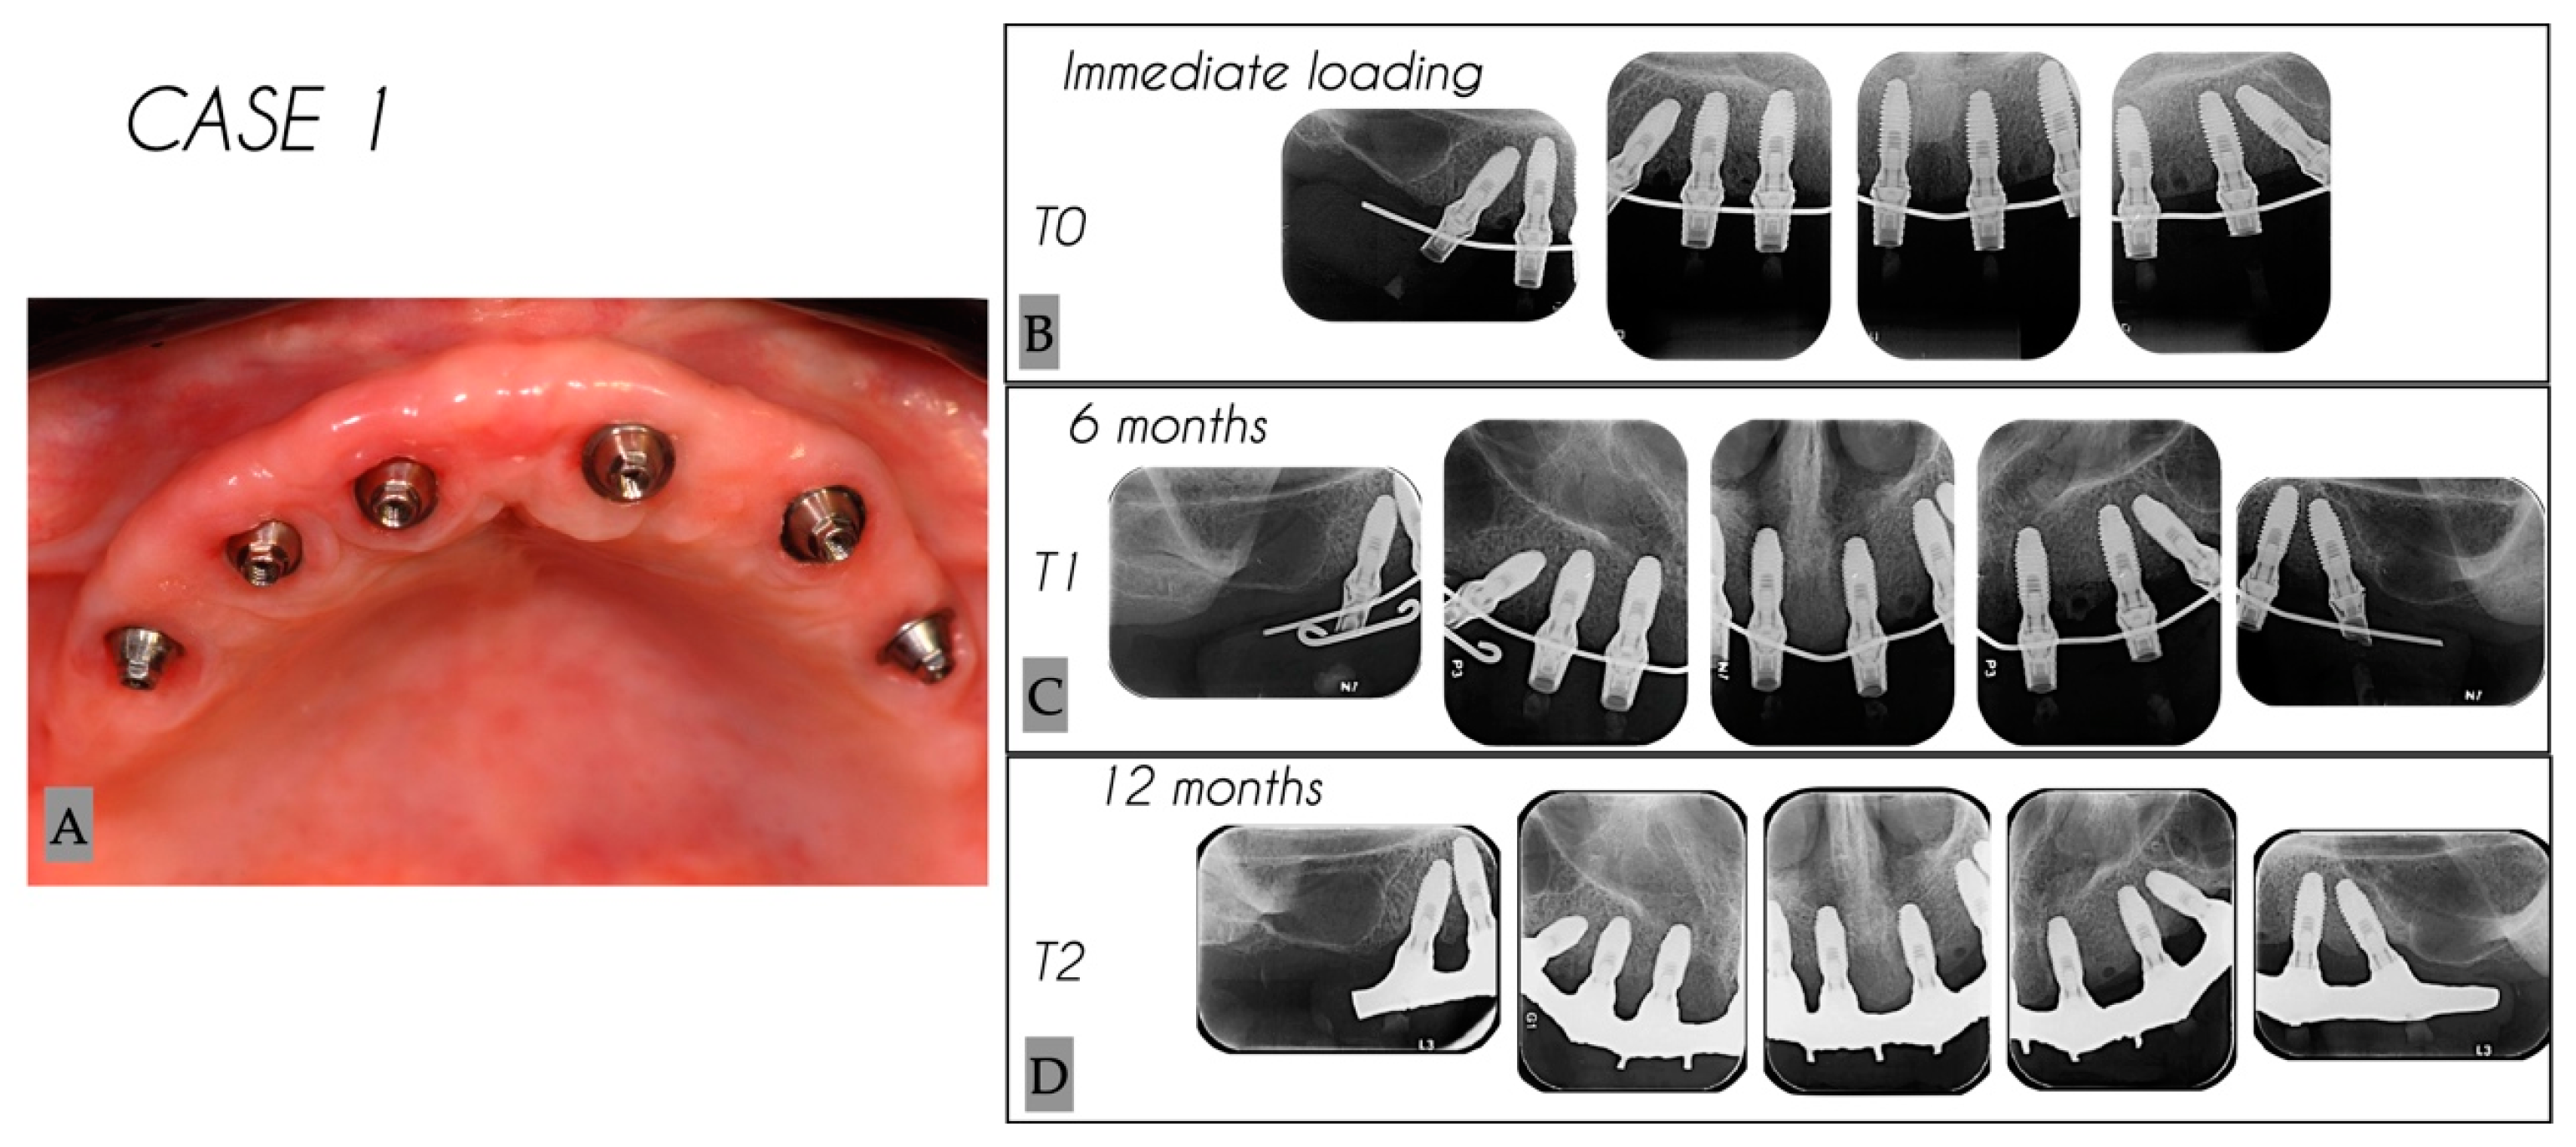

| 1 | 25 | 0.12 | 2.51 | 2.73 | 3 | 3 |

| 1 | 23 | 0 | 1.85 | 2.73 | 4 | 4 |

| 1 | 22 | 0.08 | 0.21 | 0.37 | 3 | 3 |

| 1 | 12 | 0.32 | 0.33 | 0.36 | 3 | 3 |

| 1 | 13 | 0 | 0.37 | 0.53 | 4 | 4 |

| 1 | 15 | 0.12 | 2.09 | 2.34 | 4 | 4 |

| Mean | 0.06 | 1.23 | 1.51 | 3.5 | 3.5 | |